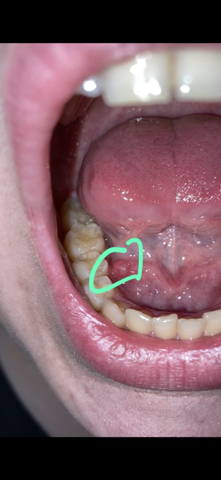

Blase an der zungenspitze. Selten kann auch die Zungenspitze betroffen sein. Schmerzhafte Entzündungen hingegen deuten auf Aphthen hin und diese entstehen an der Zungenspitze und machen sich bis zum Zungenrand breit. Bei einer Zufuhr von Nahrung oder Flüssigkeit werden die Schmerzen meist noch unerträglicher.

Doch es können sich auch Bläschen auf der Zunge zeigen die einige Zeit bestehen bleiben und meistens schmerzhaft sind. Blase auf der Zunge - die Ursachen Haben Sie etwas zu heiß gegessen können Sie sich die Zunge verbrennen. Die Bläschen werden manchmal auch als Lügen-Bläschen bezeichnet.

Blasen auf der Zunge sind sehr kleine runde bis ovale Bläschen die mit Flüssigkeit gefüllt sind. Der Schmerzcharakter kann dabei von einem Pulsieren bis zu einem Brennen variieren. Der brennende Schmerz kann dabei auf einen bestimmten Bereich der Zunge beschränkt oder diffus über der ganzen Zunge zu spüren sein.

Dann leidest du vielleicht an einer verbreiteten Krankheit namens transiente Zungenpapillitis. Der medizinische Fachbegriff für Bläschen auf der Zunge ist Vesikel. Erste Symptome eines Zungenkrebses.

Ein Brennen an der Zungenspitze bzw. Bereitet ein Tumor an der Zunge den meisten Betroffenen anfangs noch keine Beschwerden so wächst die Geschwulst mit der Zeit immer weiter heran.

Schmerzen an der Zungenspitze sind als unangenehme Empfindungen im vorderen Drittel der Zunge definiert. Der medizinische Fachbegriff für Bläschen auf der Zunge ist Vesikel. Meine Tochter 9 Monate hat seit heute eine weiße minimal gelbliche Blase an der Zungenspitze. Sie ist gut drauf kein Fieber Hände und Füße unauffällig. Neben Sprache und Geschmacksempfinden ist sie oft ein primärer Indikator für Ihre allgemeine Gesundheit. Bläschen auf der Zunge. Schmerzhafte Entzündungen hingegen deuten auf Aphthen hin und diese entstehen an der Zungenspitze und machen sich bis zum Zungenrand breit. Wer zu heißt gegessen hat der hat sich im wahrsten Sinne des Wortes die Zunge verbrannt und eine Blasenbildung entsteht. Erste Symptome eines Zungenkrebses.

Selten kann auch die Zungenspitze betroffen sein. Doch es können sich auch Bläschen auf der Zunge zeigen die einige Zeit bestehen bleiben und meistens schmerzhaft sind. Bläschen auf der Zunge. Der medizinische Fachbegriff für Bläschen auf der Zunge ist Vesikel. Die erweiterten Symptome einer vorgefallenen Blase gehören ein Vorsprung der einen Golfball-Größe Klumpen in der Öffnung der Vagina schafft Schmerzen im Beckenbereich die während des Geschlechtsverkehrs die nicht kontrolliert werden kann immer schlimmer wird beim Wasserlassen Schmerzen die in zurück stammt der untere und beginnt um mehr von den Rücken und schmerzhaften Infektionen der Blase. Ein Brennen an der Zungenspitze bzw. Die gesunde Zunge verfügt über eine blass-rosa Farbe sowie eine regelmäßig feuchte und etwas raue Oberfläche.